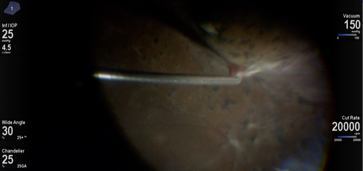

HYPERVIT Vitrectomy

Kourous A. Rezaei MD